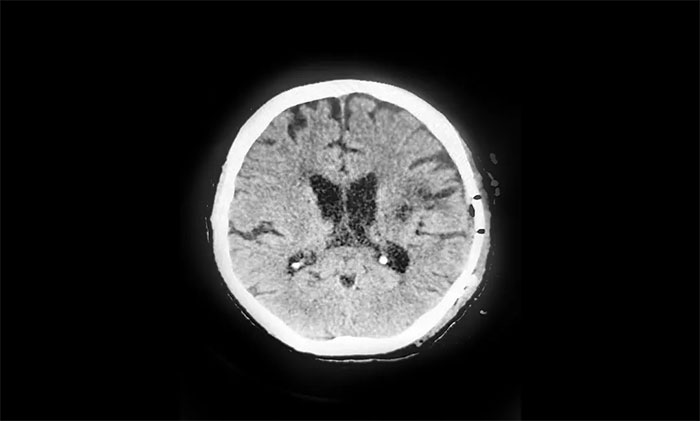

2021年10月19日晚,正在做家务的吴先生突然出现右侧肢体乏力,伴言语不利。匆忙送至苏州当地医院检查,头颅CT见左侧颞顶叶出血破入脑室。随后经完善检查、排除禁忌,在当地医院施行了“颅内血肿清除术+去骨骨瓣减压术”。

▲ 术后影像显示“复原”后的颅骨